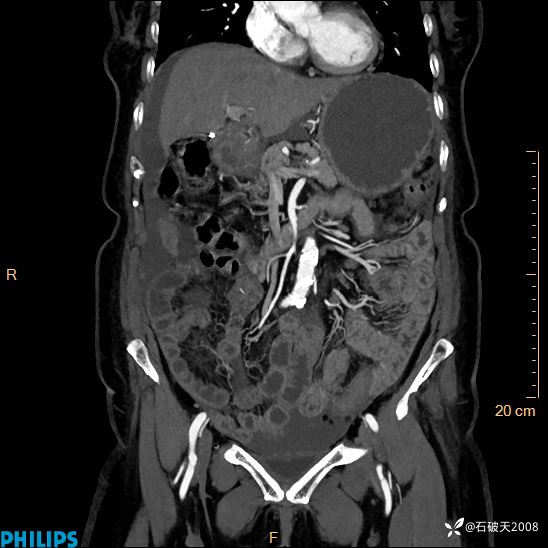

MIP